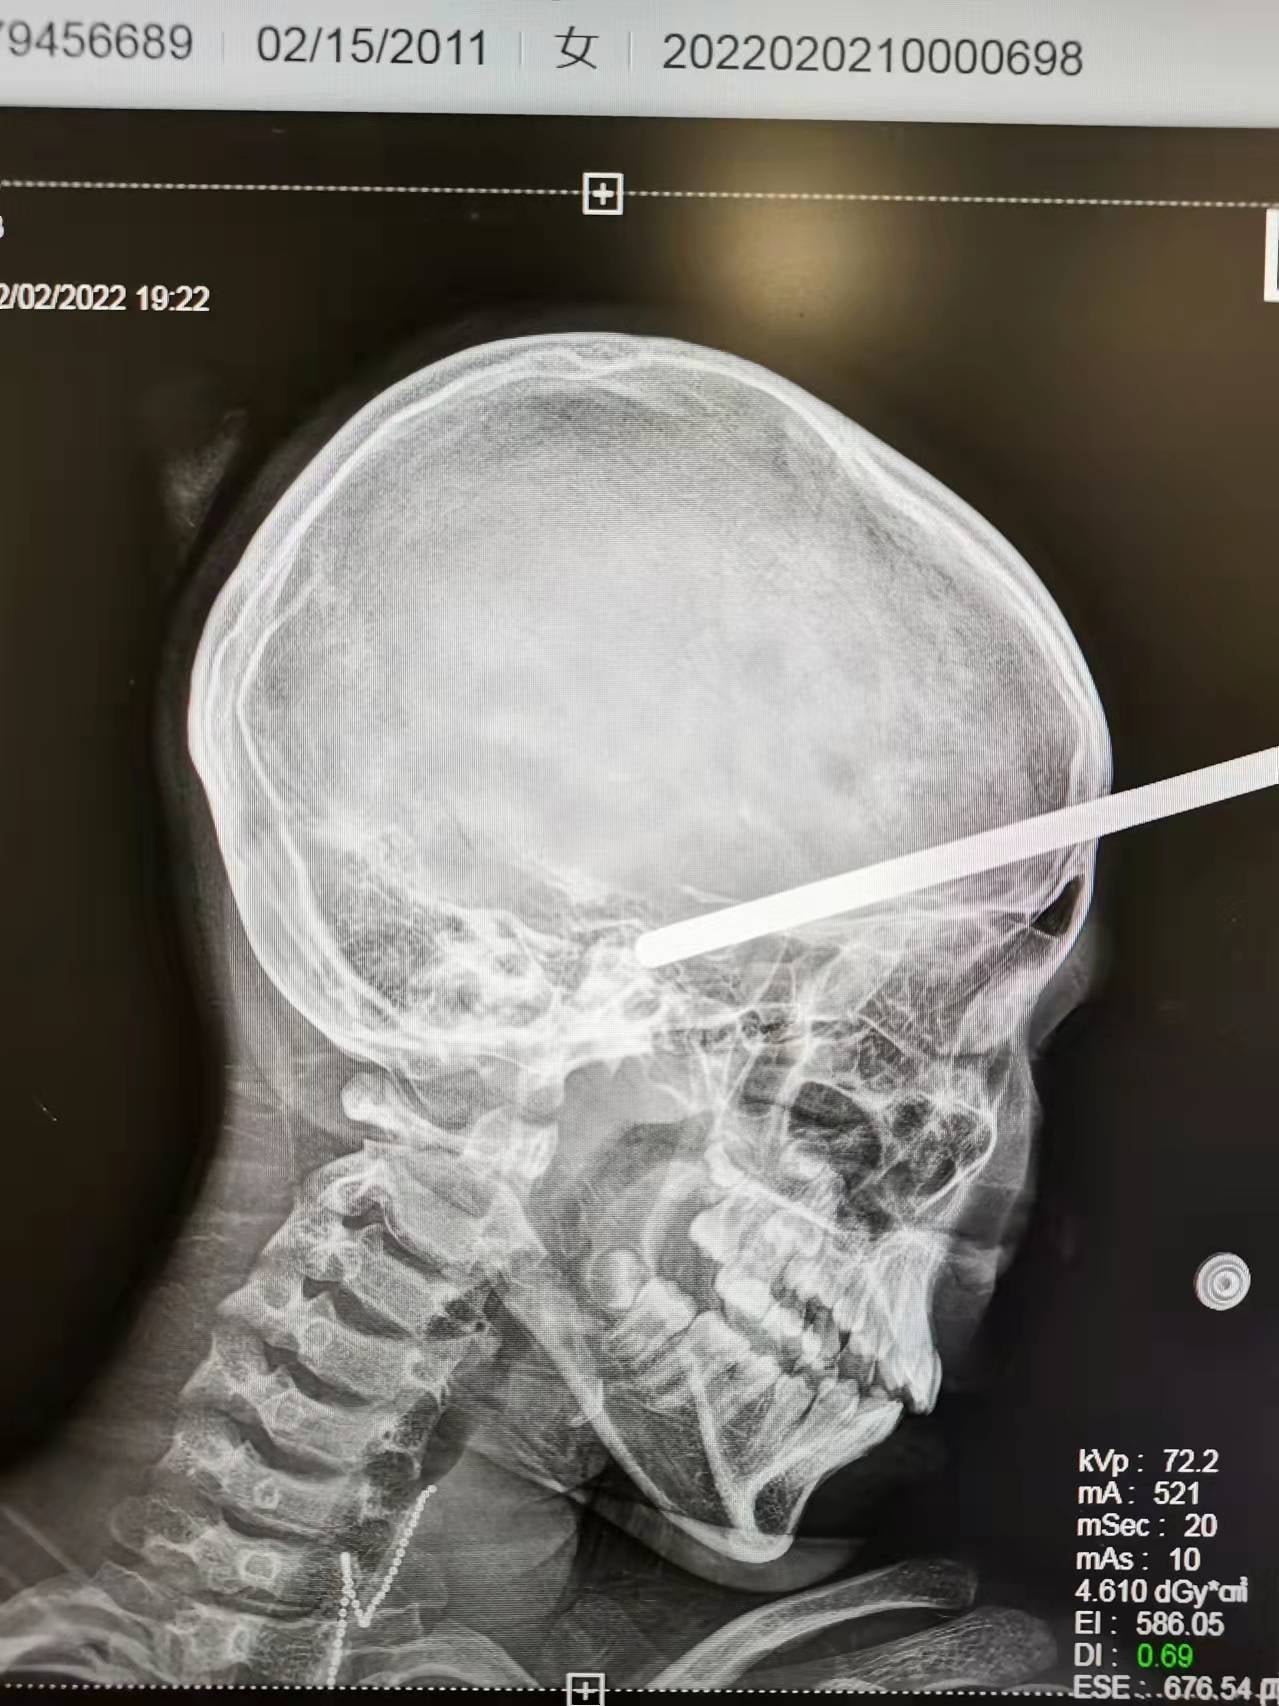

大年初二逛商场滑倒撞货架 铁棍插头颅女童险死

(上海4日讯)中国上海一名10岁女童周三(2日)与家人逛商场时,突然脚底打滑扑倒,头部撞上货架,架上的空心铁棍直插头颅,当场因疼痛哭喊,所幸是仍然意识清醒,赶紧送院抢救,经手术後目前恢复情况良好,手脚活动正常。

据外媒报道,上海新华医院周四(3日)透露,女童静静日前与母亲及姨姨在商场闲逛,不料静静突然滑倒,被货架上悬挂商品的一根细长圆柱形空心铁棍直插脑里,她即时因痛楚而大哭,意识仍然清醒,可以正常对答。

家人随即报警将静静送医,她送院时未有抽搐痉挛丶发热等不适症状,院方为她注射破伤风针及扫描其头丶胸,再安排进行微创开颅手术,取出铁棍及止血,整个手术历时2个小时。